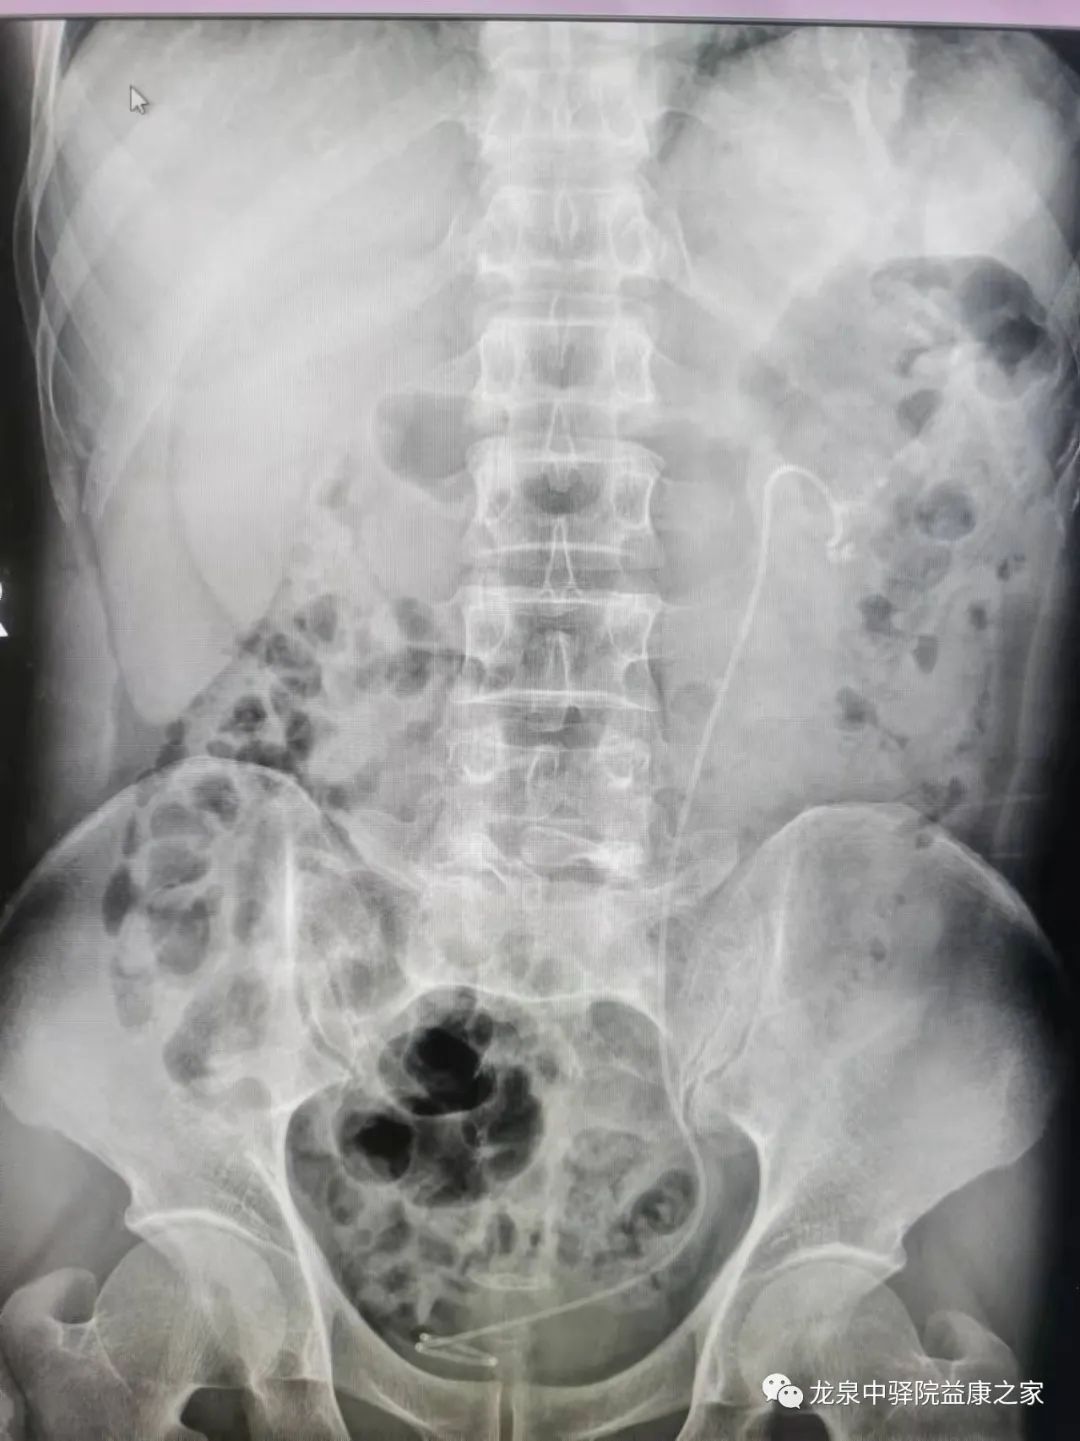

曾文彤教授无积水肾结石经皮肾手术术前CT阅片指导。

讲座结束后,曾文彤教授现场对一例无积水型肾铸形结石患者进行了现场会诊,详细指导患者的综合治疗方案和经皮肾镜手术技术要点;

此次的指导会诊手术为择期手术,患者为无积水铸形肾结石,经皮肾穿刺难度大、风险高。以往此类患者只能转到上级医院,而此次医联体单位之间合作,由上级医院专家现场进行指导诊治,制定手术方案,使得手术顺利完成,不仅保障了患者的医疗安全,而且也对基层诊疗技术水平提升提供了强大助力,让广大居民在家门口就能享受到三级甲等综合医院的医疗服务。